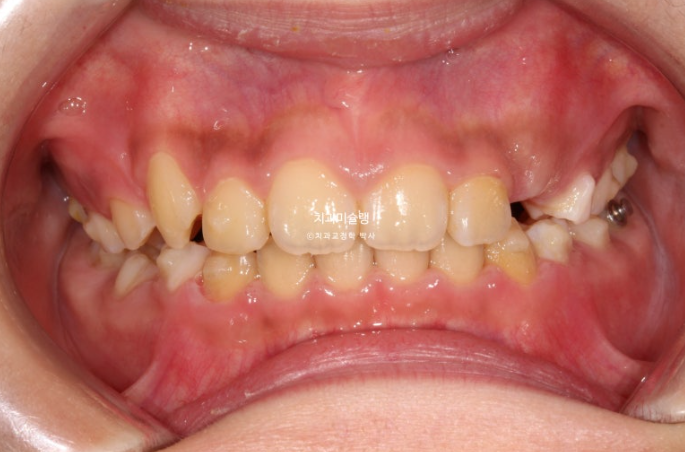

2년 전 교정치료를 위해 온 만 10세 어린이 입니다.

앞니가 하나 들려있고 깊게 물리는 과개교합이 있습니다.

중심선 불일치도 보입니다.

윗니 돌출이 측면에서 잘 보이네요.

영구치날 공간은 비교적 양호한 편입니다.